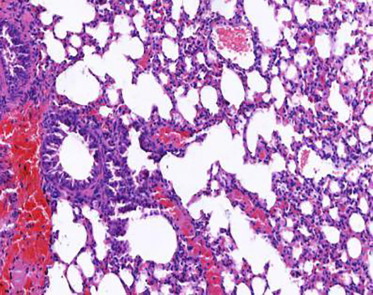

【动物造模】-五味子糖浆对支气管哮喘小鼠模型有哪些影响?

支气管哮喘是一种常见的慢性气道炎性疾病,其特征是长期复发...